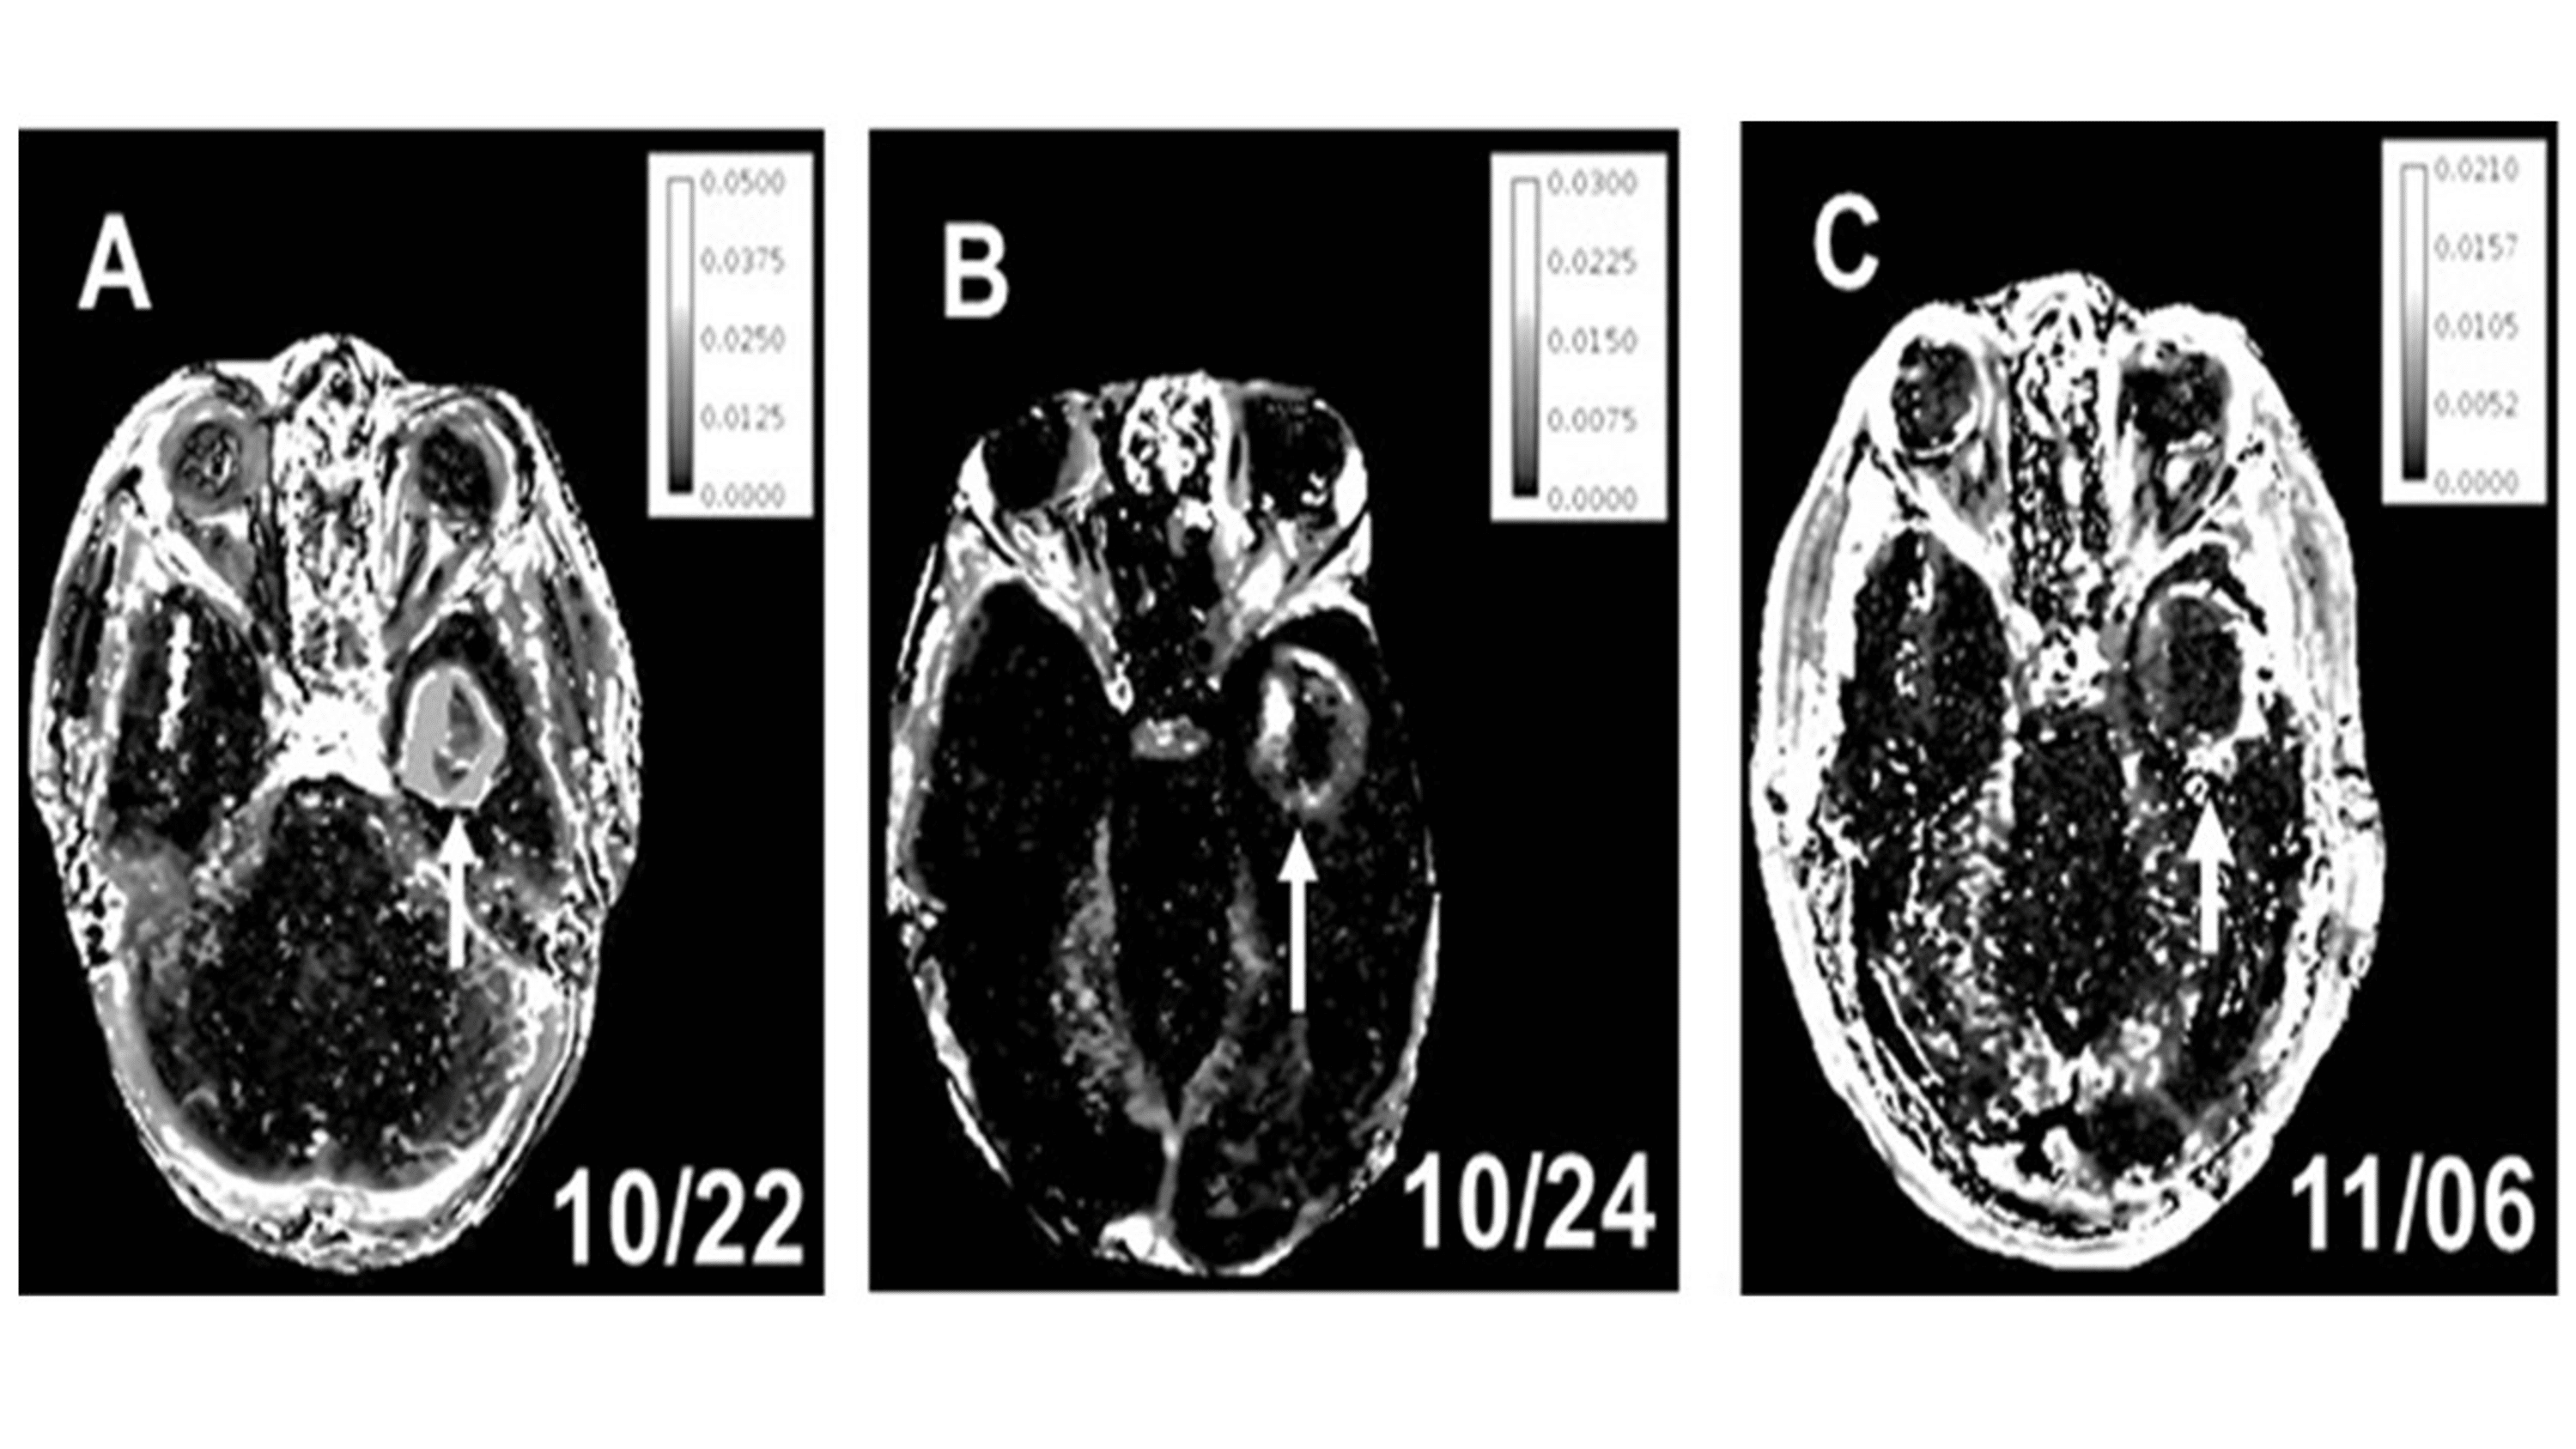

From www.cureus.com

Cureus Persistent PeriAblation BloodBrain Barrier Opening After Are There Blood Tests For Brain Tumors Brain tumors originate from abnormal growth in brain cells and the tumor itself does not release. No, blood tests cannot confirm or detect the presence of a brain tumor. Benign brain tumors account for about 71% of all brain tumors. Magnetic resonance imaging (mri) and computed tomography (ct) scans are used most often to look for brain diseases. Blood tests. Are There Blood Tests For Brain Tumors.

Cureus Persistent PeriAblation BloodBrain Barrier Opening After Are There Blood Tests For Brain Tumors Blood tests can also help in assessing some types of brain tumors, and a lumbar puncture may help in diagnosing metastatic (aggressively spreading) tumors in the brain. Benign brain tumors account for about 71% of all brain tumors. Blood tests can help to diagnose some types of neuroendocrine tumours. They develop as a mass of noncancerous cells that grow inside. Are There Blood Tests For Brain Tumors.